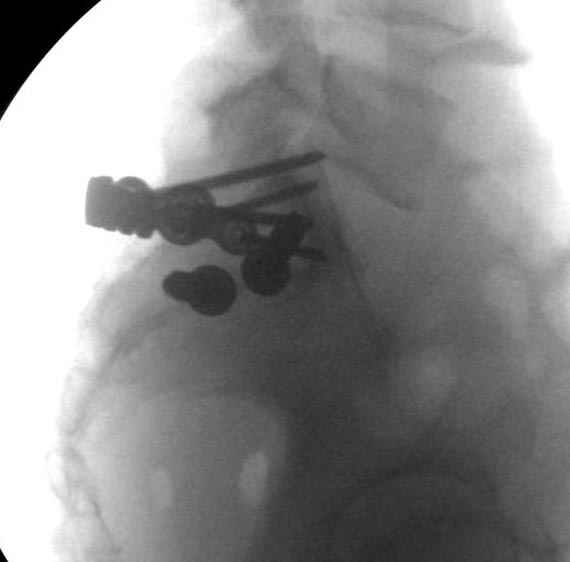

Здесь слайды случая больного с политравмой, включающей сегментарный перелом бедра и повреждение таза с нарушением тазового кольца, разрыв симфиза и перелома крестца зон 2 и 3.

На множественных слайдах важные моменты операции. Хотел бы подчеркнуть, как важно иметь возможности всех необходимых ренгенограмм, включая компютерную томографию и стандартных внутритазовых рентгенограмм (инлет и оутлет).